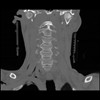

13 P.BLANDAS,,Coronal,2.000,P.BLANDAS,Coronal,